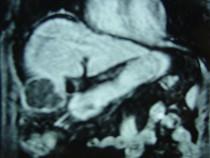

问题 男性,60岁,右上腹胀不适,右肝区叩击痛,影像检查如图,最可能的诊断是()

选项 A.肝硬化 B.肝硬化、外生性肝癌 C.肝硬化、腹腔间质瘤 D.肝硬化、膈下脓肿 E.肝硬化、结节性增生

答案 B